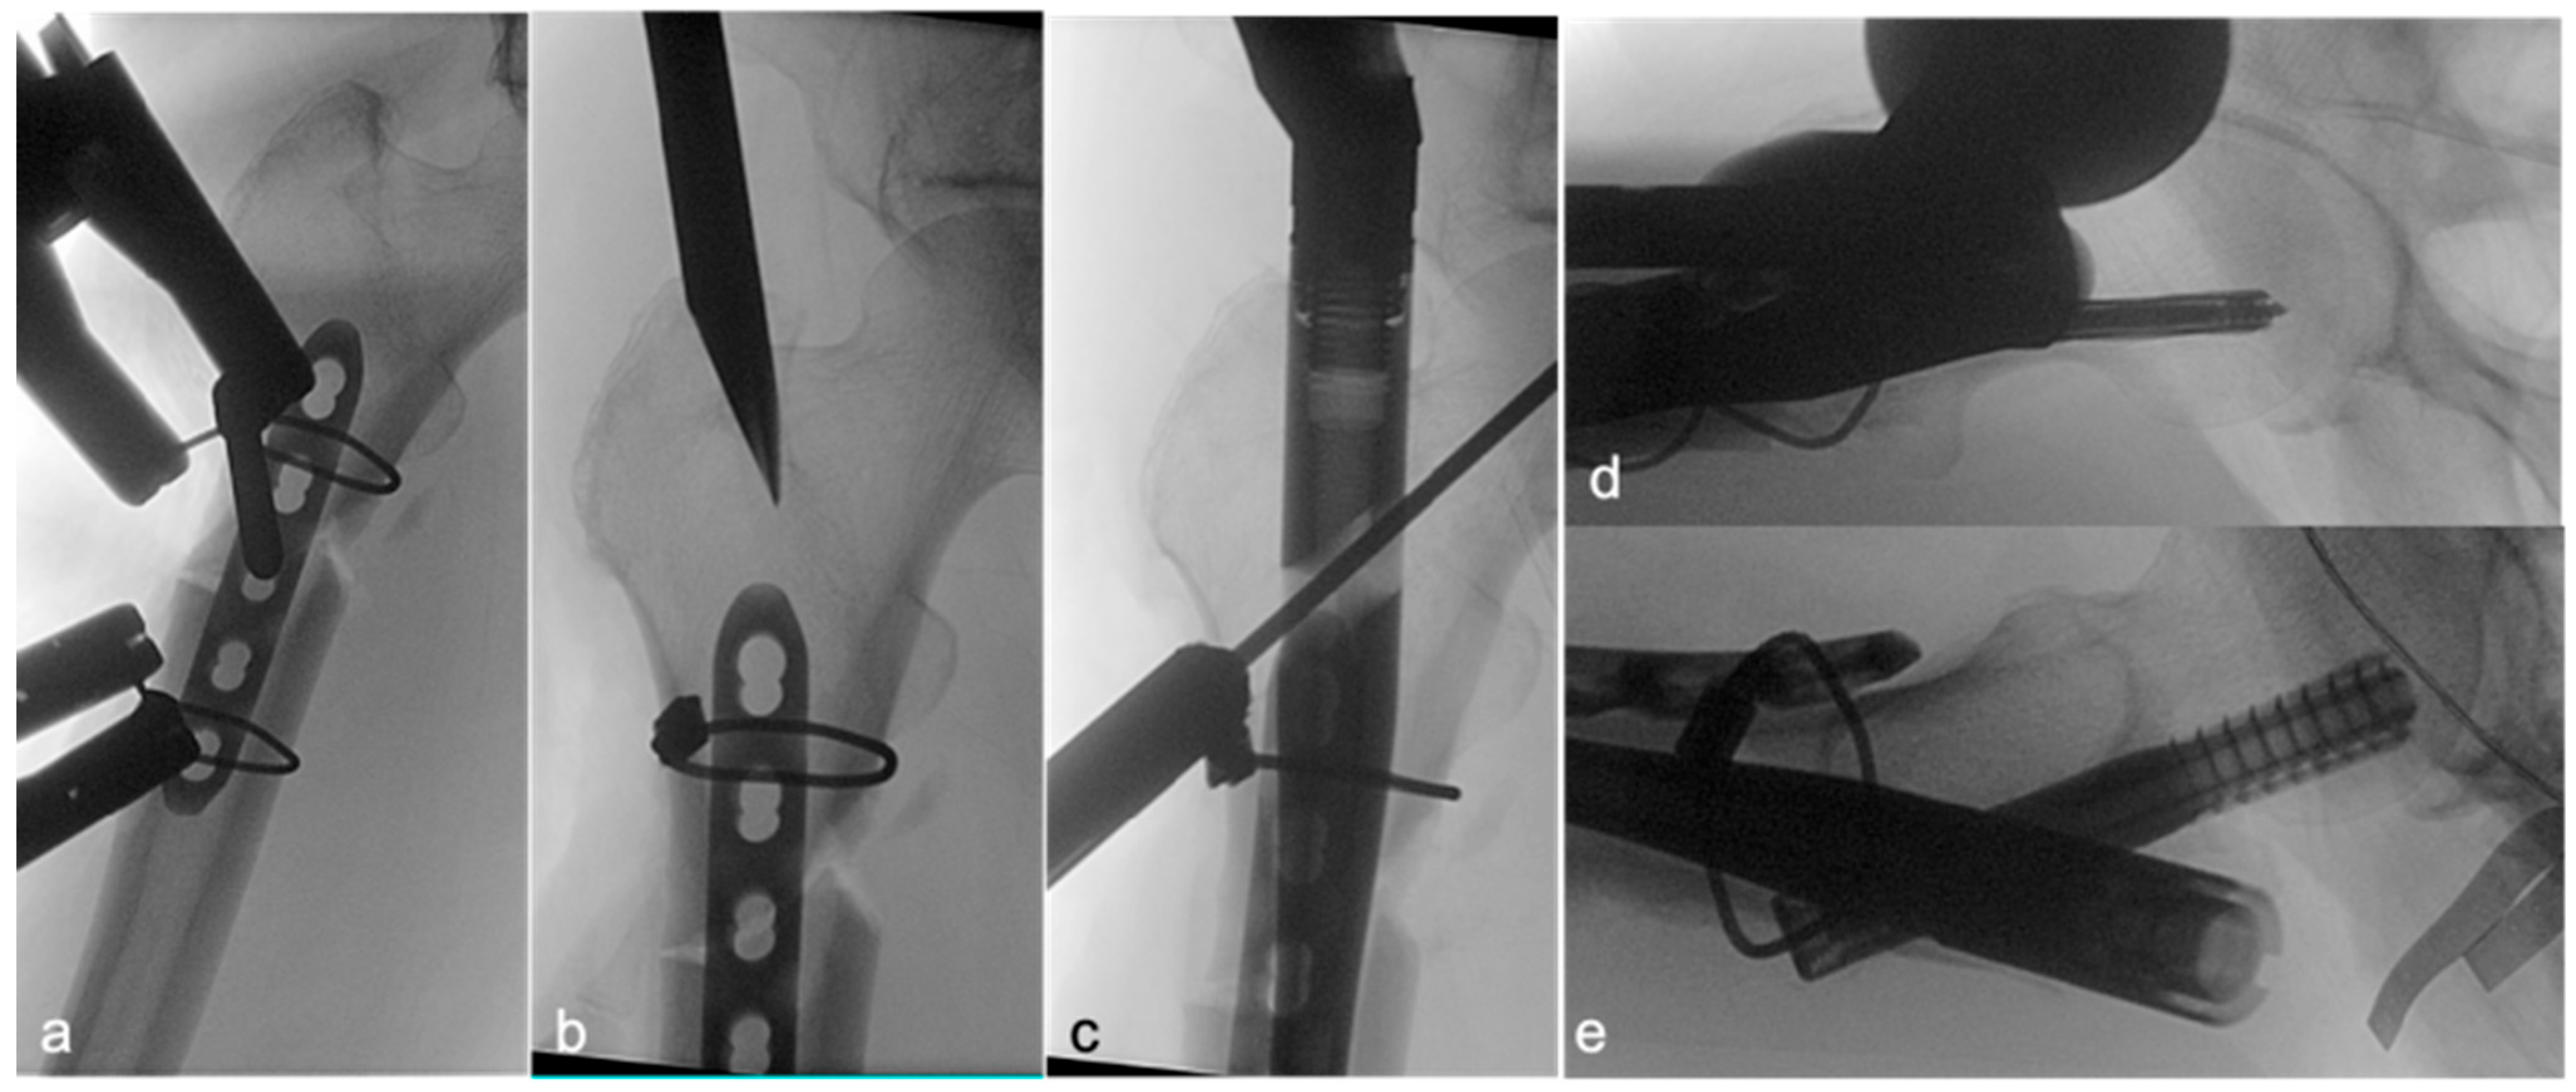

Following satisfactory reduction, a 4–5-hole narrow locking compression plate (LCP; DePuy Synthes; Raynham, MA, USA) was carefully contoured to conform to the anterolateral aspect of the proximal femur, spanning the fracture. The plate was provisionally stabilized and subsequently secured definitively to the femur using two Dall–Miles cable systems (Hankil Co., Ltd.; Gimpo-si, Gyeonggi-do, Republic of Korea). The placement and security of the plate were confirmed by intraoperative C-arm imaging (Figure 2a) and direct clinical inspection of the implant–bone interface at the fracture site (Figure 3a).

Once the lateral plate was securely fixed, providing augmented stability and maintaining the reduction, a guide pin for the cephalomedullary nail (CMN) (Zimmer; Warsaw, IN, USA) was inserted through the standard trochanteric entry point under fluoroscopic guidance (Figure 2b). The medullary canal was then reamed according to standard technique. Subsequently, the CMN was carefully inserted across the fracture site, passing alongside the prepositioned augmentative plate. The proximal fixation of the nail was achieved by inserting a cephalic/lag screw into the femoral head and neck, with its trajectory and depth confirmed by fluoroscopy (Figure 2c,d). Finally, two distal interlocking screws were placed through the nail to secure the distal fixation. The completed dual-fixation construct, ensuring satisfactory fracture alignment, implant stability, and overall mechanical integrity, was verified with final C-arm images (Figure 2e) and direct intraoperative visualization of the stabilized fracture site prior to wound closure (Figure 3). Postoperative rehabilitation protocols were standardized for both groups, with weight-bearing restrictions guided by radiographic evidence of healing and surgeon discretion.

Figure 2. Key intraoperative C-arm images illustrating the surgical sequence of intramedullary (IM) nailing with lateral plate augmentation for an atypical subtrochanteric femoral fracture. (a) (AP) The contoured lateral plate is secured to the femur using two Dall–Miles cable systems. (b) (AP) Following initial fracture reduction and plate fixation, the guide pin for the intramedullary nail is inserted into the proximal femur. (c) (AP) Targeting for the cephalic/lag screw of the intramedullary nail. (d) Placement and confirmation of the cephalic/lag screw (lateral). (e) The completed dual-fixation construct, showing the intramedullary nail with proximal locking, and the augmentative lateral plate in situ, confirming satisfactory fracture alignment and implant positioning (lateral).